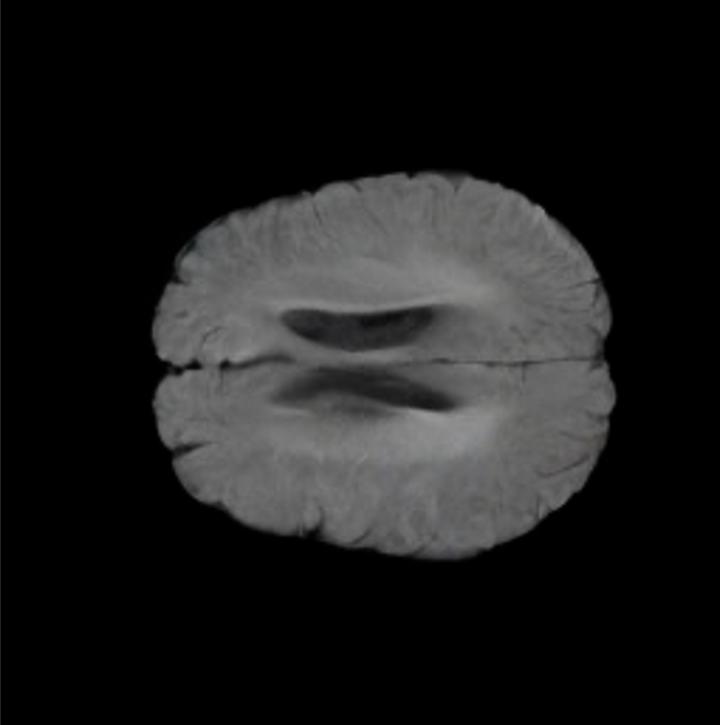

Notably, X-Diffusion achieves sota dB for a few input slices while baselines require more than 60 input slices to achieve similar performance (Figure 7). The margin is more than 12 dB PSNR for the 1-slice input in both the BRATS and the UK Biobank benchmarks (see Table 1 and Figure 6). For reference, two randomly sampled MRIs from the UK Biobank would have a PSNR of 15.95 dB 0.36 (on 4800 randomly sampled examples). The slices from 3D reconstructed volumes at varying depths and axis of rotation visually match the ground truths (see Figures 5 and Figure 4). We also plot the error map (Figure 4) of such X-Diffusion generations to highlight the differences with the ground truth MRIs.

Brain Volumes Preservation. The generated MRIs by our X-Diffusion retain almost the exact same average brain volume vs of the real MRIs.

The comparison of generated MRIs versus reference MRIs suggests a nearly perfect preservation of brain volume (in mm3) with median volume of reference MRIs of versus generated MRIs (see an example of brain generation in Figure 11).